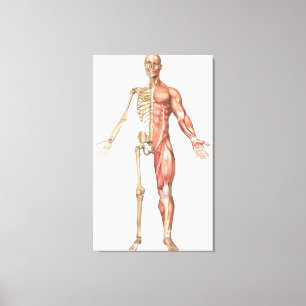

Lienzo Ilustracion médico del sistema muscular masculino

Precio 187,00 €